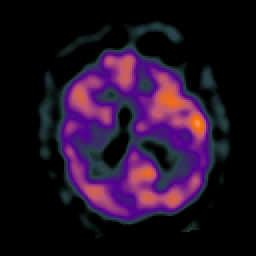

Subacute Stroke, overlay -- Slice #15

[Home][Help][Clinical] Slice 15